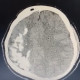

ALO Dokter. Laki-laki 24 tahun dengan kejang fokal berulang dan gangguan kognitif. Hasil CT scan mempelihatkan gambaran berikut:

Apakah sejawat mengenali gambaran khas CT scan tersebut?

Apa kemungkinan diagnosis yang paling mungkin ?

Dan PF khas apakah yang sejawat dapat temui pada kasus ini?

Gambara diatas disebut sebagai tram track sign yaitu kalsifikasi di regio kortikal otak khas pada sindrom Sturge Weber disertai hemicerebral atrophy.

Pada pemeriksaan fisik biasanya kita akan menemukan port wine stain pada area wajah pasien.